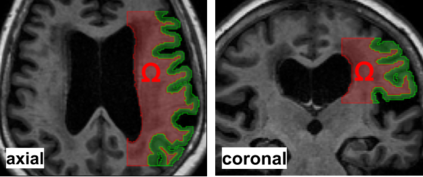

In recent years, a plethora of methods combining deep neural networks and partial differential equations have been developed. A widely known and popular example are physics-informed neural networks. They solve forward and inverse problems involving partial differential equations in terms of a neural network training problem. We apply physics-informed neural networks as well as the finite element method to estimate the diffusion coefficient governing the long term, i.e. over days, spread of molecules in the human brain from a novel magnetic resonance imaging technique. Synthetic testcases are created to demonstrate that the standard formulation of the physics-informed neural network faces challenges with noisy measurements in our application. Our numerical results demonstrate that the residual of the partial differential equation after training needs to be small in order to obtain accurate recovery of the diffusion coefficient. To achieve this, we apply several strategies such as tuning the weights and the norms used in the loss function as well as residual based adaptive refinement and exchange of residual training points. We find that the diffusion coefficient estimated with PINNs from magnetic resonance images becomes consistent with results from a finite element based approach when the residuum after training becomes small. The observations presented in this work are an important first step towards solving inverse problems on observations from large cohorts of patients in a semi-automated fashion with physics-informed neural networks.